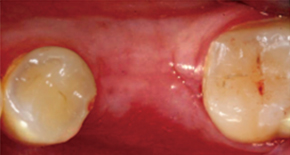

4. Suture

5. Recovery

6. Re-incision

7. Healing Abutment/SuturePain and swelling can be minimized and quick return to daily life is possible.